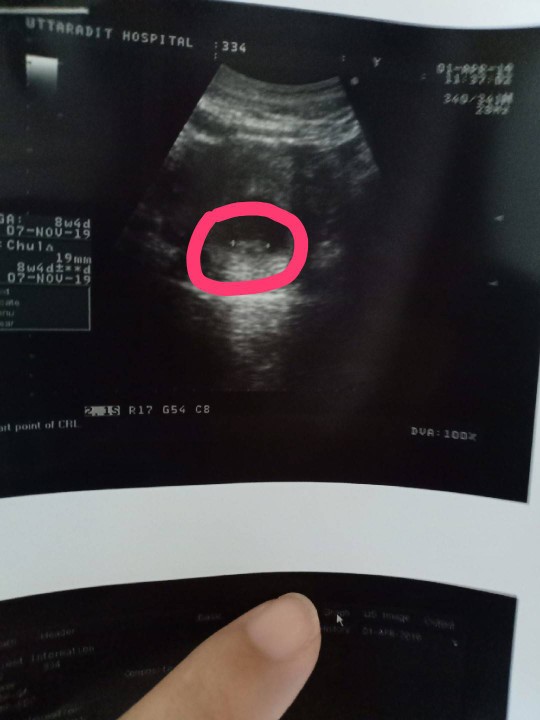

5ใคร5วัน เห็นหัวใจกระพริบๆแล้วค่ะ ซาวช่องคลอดนะค่ะ

8wks

ถ้ารีบไปฝากครรภ์เลย หมอจะซาวให้ทันทีค่ะ บางคน 6w ก็เจอตัวน้องแล้วค่ะ บ้านนี้ไปฝากตอน 8w ก็เจอตัวน้องค่ะ